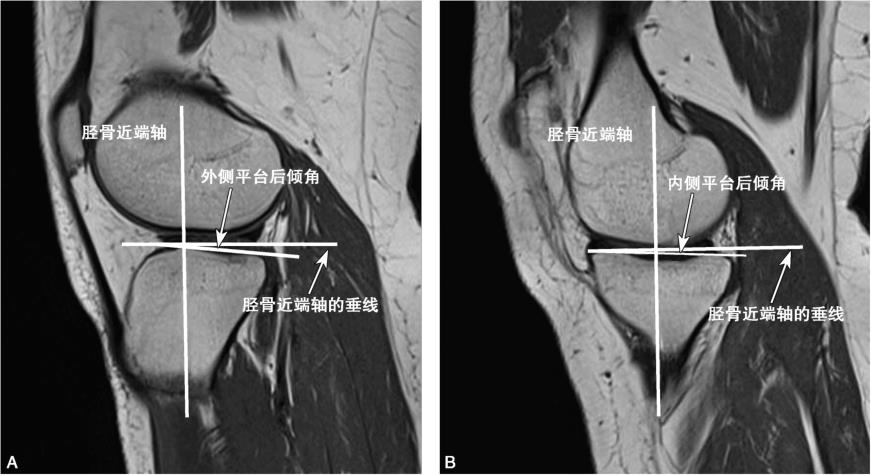

图5-6 选取测量平面

分别选取内侧平台或外侧平台中间层面测量内侧或外侧平台后倾角,AA为外侧,BB为内侧。

见图5-7。

图5-7 测量胫骨平台后倾角

胫骨平台前后缘最高点的连线与胫骨轴线垂线的夹角为胫骨平台后倾角。前后缘连线位于垂线下方为正值,否则为负值。A.外侧后倾角;B.内侧后倾角。